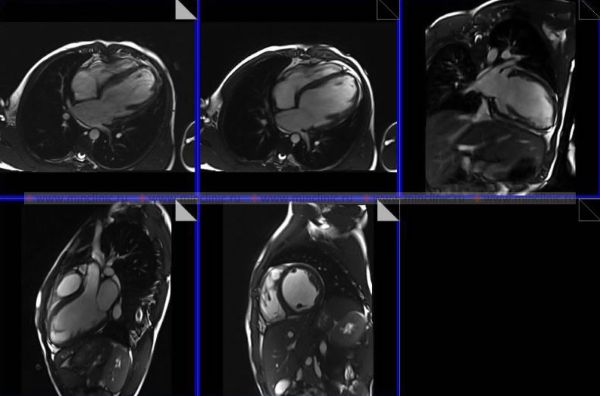

МРТ (магнитно-резонансная томография) органов грудной клетки — это способ визуализации с применением силового магнита и радиоволн, с помощью которых в дальнейшем строится изображение органов грудной клетки (сосуды, сердце, лёгкие). Во время проведения МРТ (магнитно-резонансной томографии) органов грудной клетки 3,0 Т (тесла) пациент не получает радиационного облучения (лучевой нагрузки).

МРТ (магнитно-резонансная томография) грудной клетки позволяет специалистам получить изображение расположенных там органов пациента (сердце, бронхи, лёгкие и т.д.) для оценки их функционального состояния или выявить произошедшие в них органические изменения.

- оценка органов грудной клетки в трёхмерной реконструкции под разными углами;

МРТ (магнитно-резонансной томографии) органов грудной клетки может показать следующие нарушения в сердце, лёгких или грудной клетке: